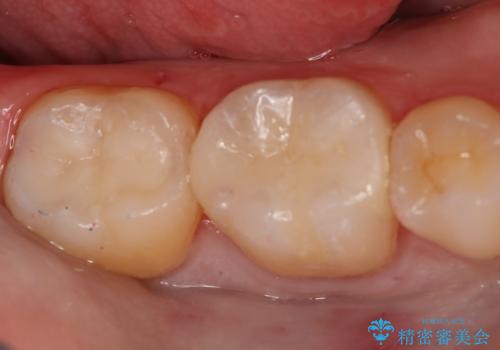

- 右下6・7番の虫歯治療を主訴に来院された患者様です。

精度が高く見た目が良いものを希望されたので、切削量・形態を考慮しセラミックインレーでの治療を計画しました。

奥歯でも下の歯の場合は審美性の高いセラミックを選択される患者様が多いです。